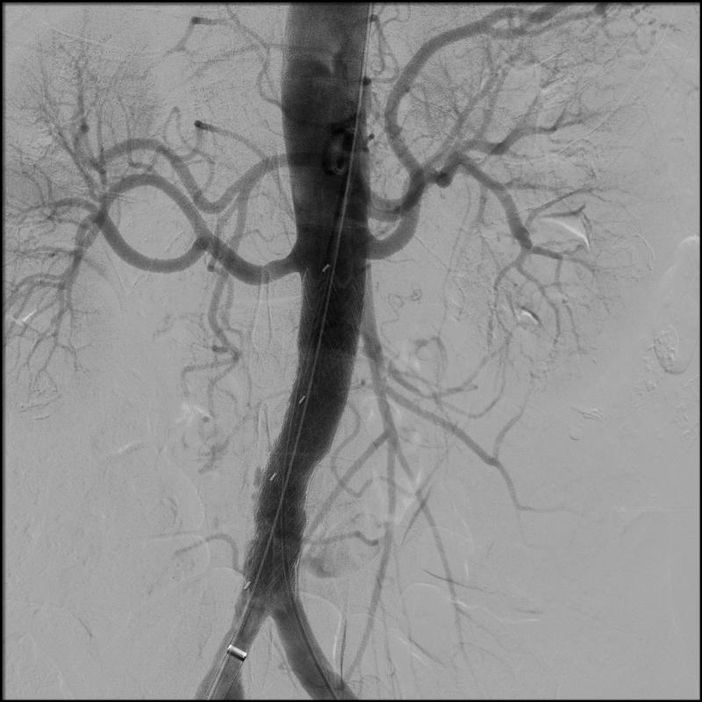

Nello specifico, “presso il nostro ambulatorio, da circa 4 anni era in follow up un paziente di 80 anni, portatore di una PAU (Ulcera Aterosclerotica Penetrante) dell’aorta addominale. In anamnesi riferiva ipertensione, dislipidemia, pregresso intervento alla prostata, cardioversione per fibrillazione alcuni anni prima e, attualmente, terapia con anticoagulante sempre, per la fibrillazione. Il paziente era asintomatico, anche all’ultimo controllo, ma abbiamo assistito a un repentino incremento della profondità della lesione che è passato in poco più di 6 mesi da 0,8 mm a 20 mm”, prosegue la dottoressa Socrate.

L’ulcera penetrante aterosclerotica (PAU) dell’aorta è una patologia che si riscontra, prevalentemente, in aorta toracica, eccezionalmente in aorta addominale (circa 1% dei casi): caratteristicamente, questa lesione si sviluppa nei pazienti anziani, con un’aterosclerosi sistemica.

In anestesia locale e sedazione, mediante un accesso mini-invasivo - percutaneo, è stata impiantata la protesi con un particolare accorgimento tecnico (invertendo la protesi su banco) che ha consentito di riparare la lesione, senza aprire l’addome.